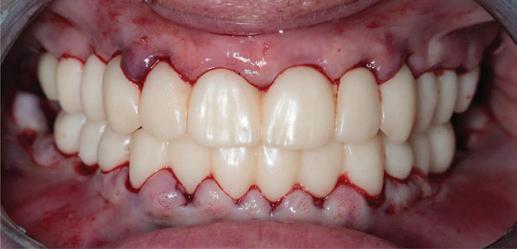

The following real case illustrates the workflow for a patient who was treated with full dentures in Abro Basic Multistratum and Denture Gingiva Basic Mono Pink.

Treatment plan

T he initial situation presented an edentulous upper jaw and a lower jaw with only the presence of tooth 43. The restorative team opted for two full dentures in Abro Basic Multistratum and Denture Gingiva Basic Mono Pink and a non-invasive zirconia crown restoration for tooth 43 with Prettau® 3 Dispersive®

Figure 4a. Before.

Figure 4b. After.